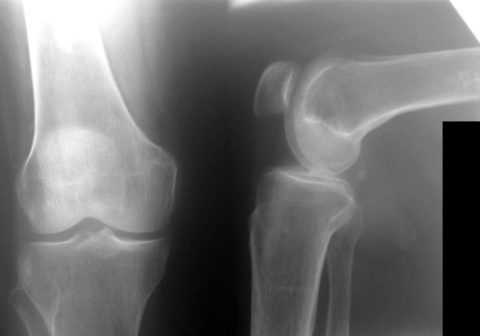

- Рентгенологическое исследование. При ревматоидном артрите выявляется остеопороз прилежащих костей, отечность мягких тканей вокруг сустава.

Подтверждается диагноз обычно рентгенологическим исследованием

Медицина диагностирует это заболевание с помощью рентгенологического метода. При этом выявляются специфические критерии:

- уплотнение мягких тканей вокруг сустава;

- костные структуры сустава видны очень чётко;

- имеются эрозивные изменения.